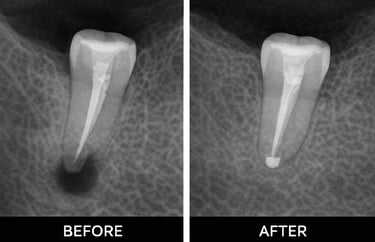

Examination & X-rays – determine the extent of infection or damage

Root canal treatment removes infected or damaged pulp from inside a tooth. The pulp contains nerves and blood vessels, and infection can cause pain, swelling, or abscesses. During the procedure, the dentist cleans out the infection, shapes the root canals, and fills them with a safe material. Finally, the tooth is restored with a crown or filling to protect it. Root canals prevent infection from spreading and help keep your natural tooth